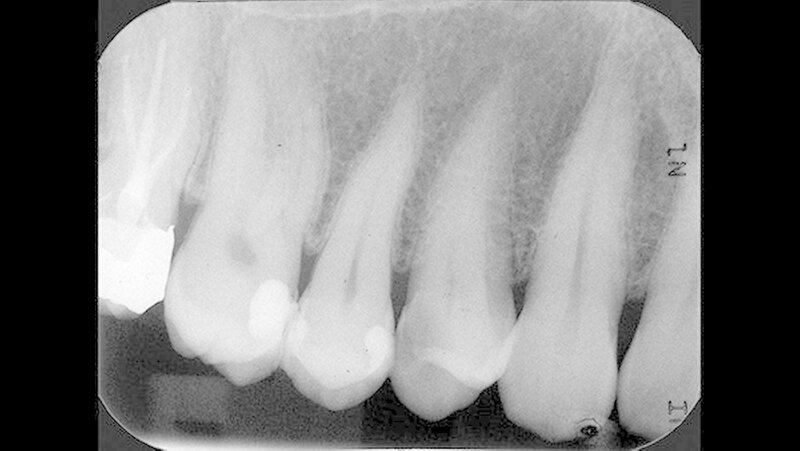

Bei den Kontrolluntersuchungen sechs und 26 Monate nach direkter Überkappung war der Zahn 14 klinisch unauffällig (Abbildung 11) und zeigte sich wiederum bei der Sensibilitätsprobe mit CO

2

-Schnee positiv und bei der Perkussionsprobe negativ.

Auf dem 26 Monate nach direkter Überkappung angefertigten Zahnfilm konnten apikal an Zahn 14 keine pathologischen Veränderungen festgestellt werden (Abbildung 12). Dem Patienten zufolge war es zu keinem Zeitpunkt, zum Beispiel im Kontakt mit kalter Nahrung, Flüssigkeit oder Luft, nach der direkten Überkappung zu Beschwerden an Zahn 14 gekommen.